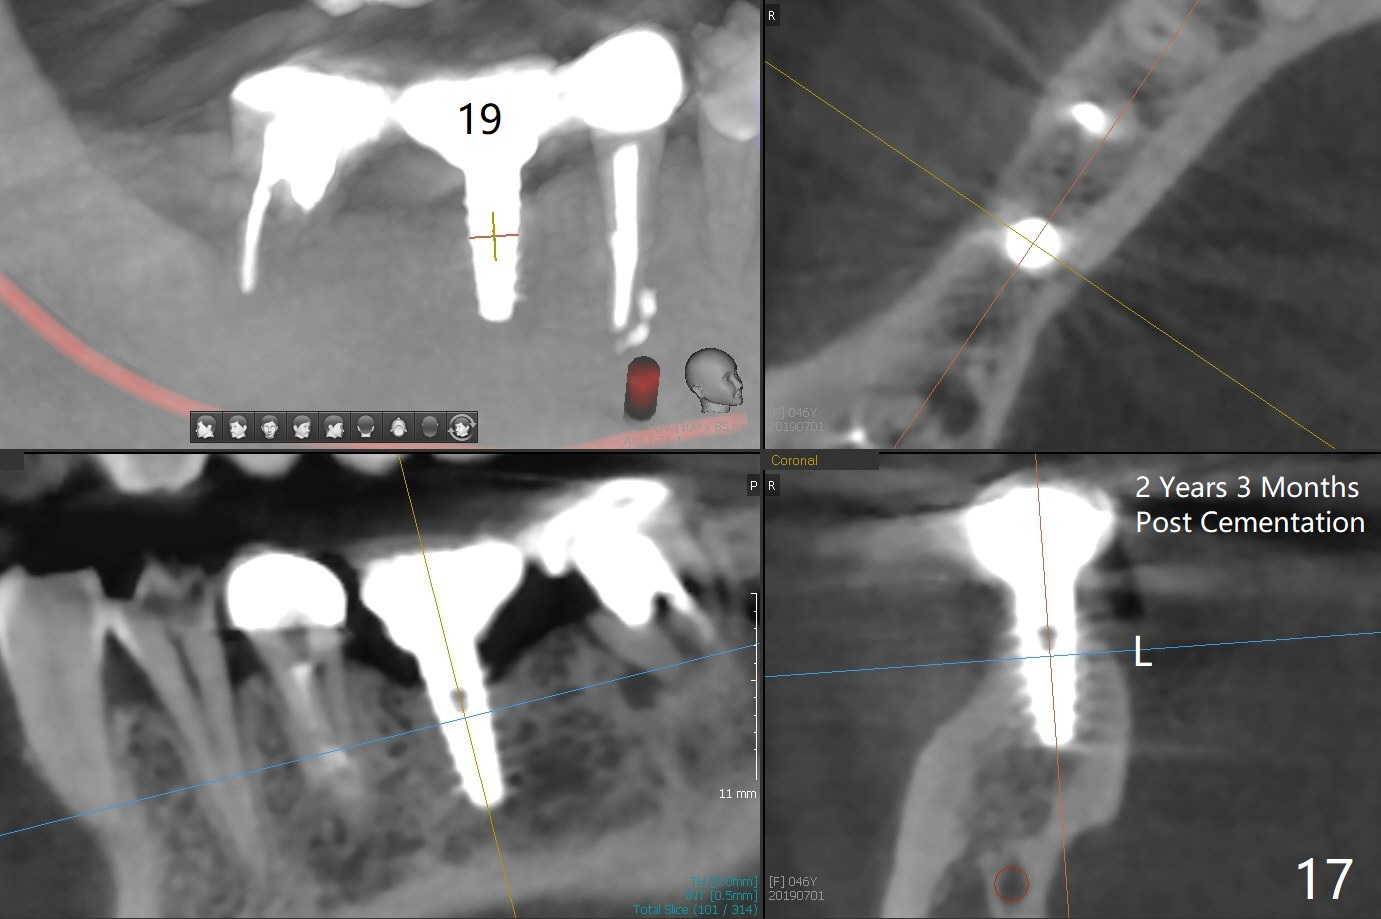

Splinted provisional is fabricated #30 and 31 one month postop. The patient returns for final restoration (single units) nearly 4 months postop (Fig.11). Since the margin is subgingival, a screw type crown is fabricated for #30 (Fig.12). The buccal gingiva looks convex after healing cap removal (Fig.13, as compared to Fig.4 (concave)). PA is taken immediately post tightening and cementation (Fig.14, 5 months postop). It appears that new bone has grown between the most coronal threads (arrows). The bone density immediately around the implant appears to increase 1.5 years post cementation (Fig.15,16). She returns because of failure of 18-20 bridge (implants will be placed at 18/19). The implant at #30 is in fact not placed deep enough; the coronal threads seem to be exposed, although there is no periimplantitis (Fig.17 CT). The tooth #31 is symptomatic; the mesial canal is missing (Fig.18 M, <). The gingiva around the crowns at #30 and 31 remains healthy 2 years 4 months post cementation (Fig.19). Metal exposure of the crown at #31 is intentional. Occlusal reduction is done to alleviate periapical re-infection (Fig.18).